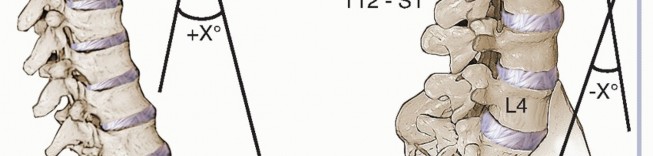

*FIG 6 • Regional lordosis and kyphosis are measured on the standing lateral radiograph. Typically, the vertebral endplates are used as **

*FIG 6 • Regional lordosis and kyphosis are measured on the standing lateral radiograph. Typically, the vertebral endplates are used as **

* **FIG 7 • Sagittal balance is evaluated on the standing lateral radiograph. It is measured as the anterior (positive) or posterior (negative) distance between the C7 plumb line and the center of the L5-S1 disc space.**